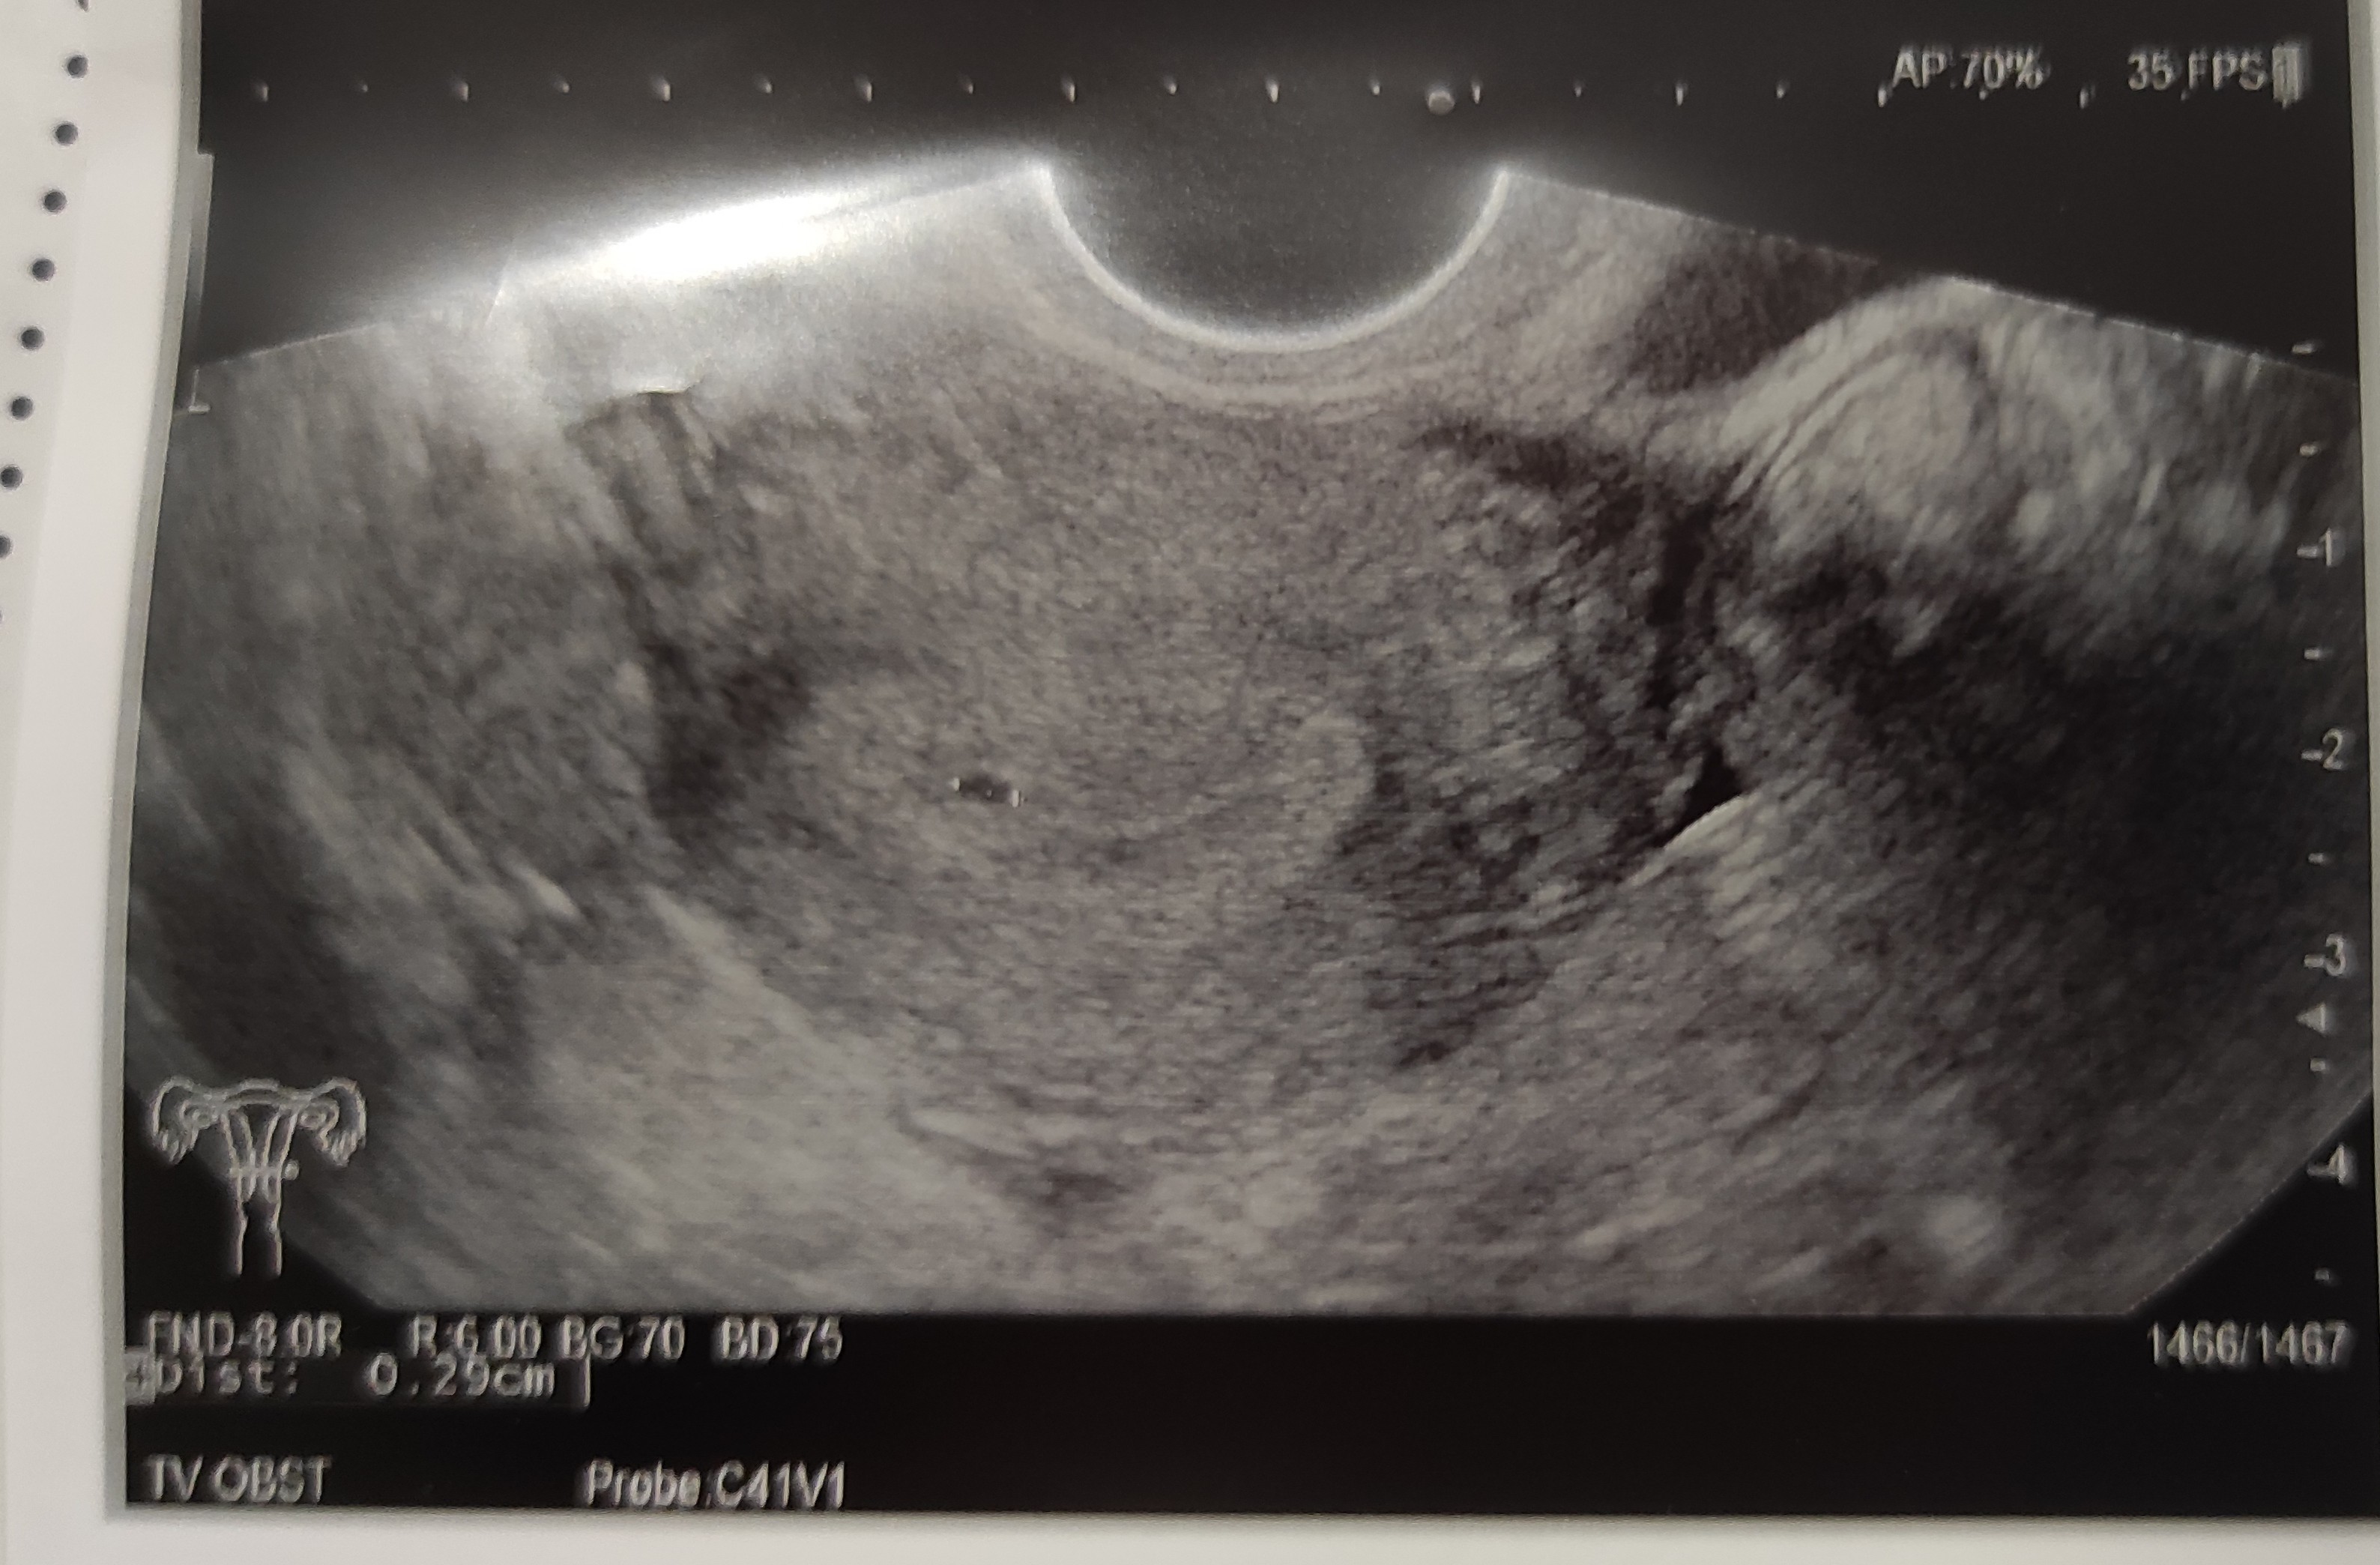

23 grudnia miałam termin spodziewanej miesiączki, nie przyszła. 24 i 25 grudnia zrobiłam testy i dwie piękne kreski na każdym. Dziś zrobiłam betę i mam 1015, co wskazuje na 5 tydzień. Poszłam do swojego lekarza, żeby umówić się na wizytę. Przyjął mnie już dziś, bo w tym cyklu miałam podany Pregnyl (wcześniej bez niego pęcherzyki w jajnikach rosły zbyt duże i zbyt późno pękały).

Niestety na wizycie pęcherzyk bardzo malutki. Z jednej perspektywy 0,29 cm, a z innej 0,19 cm). Pani Doktor powiedziała, że jest za mały na swój wiek, ale że może się rozwinąć. Mam przyjść za tydzień, 3.01.

Może jednak za bardzo się pospieszyłam i faktycznie jeszcze urośnie. To moja pierwsza ciąża. Miała któraś z Was już tak ?

@Majena94 Poszłaś jeszcze bardzo wcześnie więc się nie stresuj niepotrzebnie :) za tydzień trzymam kciuki, że już będzie pięknie wszystko widać :)

a teraz przynajmniej wiesz, że się wszystko ulokowało w macicy, więc też to jest dobra informacja :)